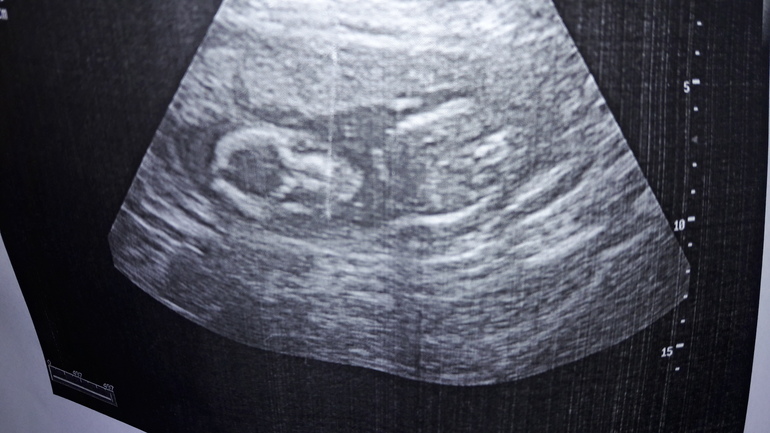

УЗИ 19нед и 1 день 12.06.17

УЗИ, КТГ, доплерНаконец-то снова увидила свою крошку тихоню.

По этому УЗИ мы опережаем уже и дату по месячным.

Ляля у нас скромняжка, и ручками пряталась, и ножки складывала.

Врач смотрел со всех ракурсов и конечный вердикт: висюлька не обнаружена) )))

Весит практически 300грамм